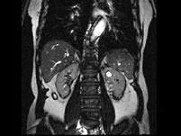

- 多项选择题男,67岁, 无痛性血尿1月,IVP和MRI检查如图示, 下列说法正确的是 ( )

B、左肾中部内侧可见类圆形不均匀信号肿块突向外

C、左肾上极可见一T

WI为高信号圆形病灶,边界清楚D、左肾中部病灶考虑为小肾癌

E、左肾上极病灶考虑为肾囊肿